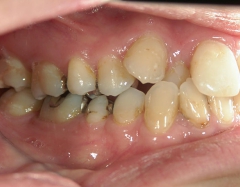

矯正歯科 治療前矯正歯科 治療前

28歳女性 浜松市中区在住

治療期間2年6ヶ月

矯正歯科 治療前 外科手術併用(コルチコトミー)、非抜歯